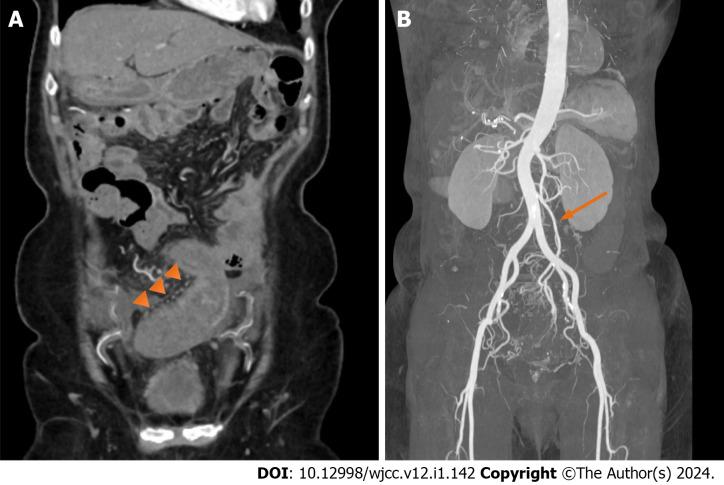

We present the case of a 68-year-old female patient who underwent laparoscopic left hemicolectomy for transverse colon cancer 3 years ago. Postoperatively, follow-up included an annual colonoscopy and abdominal computed tomography (CT) at a local clinic. However, progressive erythema and edema of the sigmoid colon were observed 1 year postoperatively. Upon admission to our hospital, she complained of abdominal pain and diarrhea. Abdominal CT showed thickening of the sigmoid colon walls, and colonoscopy revealed erythema, edema, and multiple ulcers with exudate in the sigmoid colon. CT angiography showed engorgement of the sigmoid vasa recta without any vascular abnormalities. The diagnosis was congestive ischemic colitis, and we treated the patient with anti-inflammatory agents. After 2 mo of glucocorticoid therapy (20 mg once daily) and 7 mo of 5-aminosalicylate therapy (1 g twice daily), the ulcers completely healed. She has not experienced any recurrence for 2 years.

我们报告一例68岁女性患者,她3年前因横结肠癌接受了腹腔镜左半结肠切除术。术后,在当地诊所进行的随访包括每年一次的结肠镜检查和腹部计算机断层扫描(CT)。然而,术后1年观察到乙状结肠出现进行性红斑和水肿。入院时,她主诉腹痛和腹泻。腹部CT显示乙状结肠壁增厚,结肠镜检查显示乙状结肠有红斑、水肿和多处伴有渗出物的溃疡。CT血管造影显示乙状结肠直血管充血,无任何血管异常。诊断为充血性缺血性结肠炎,我们用抗炎药对患者进行了治疗。经过2个月的糖皮质激素治疗(每日一次,每次20mg)和7个月的5-氨基水杨酸治疗(每日两次,每次1g),溃疡完全愈合。她2年来未出现任何复发。